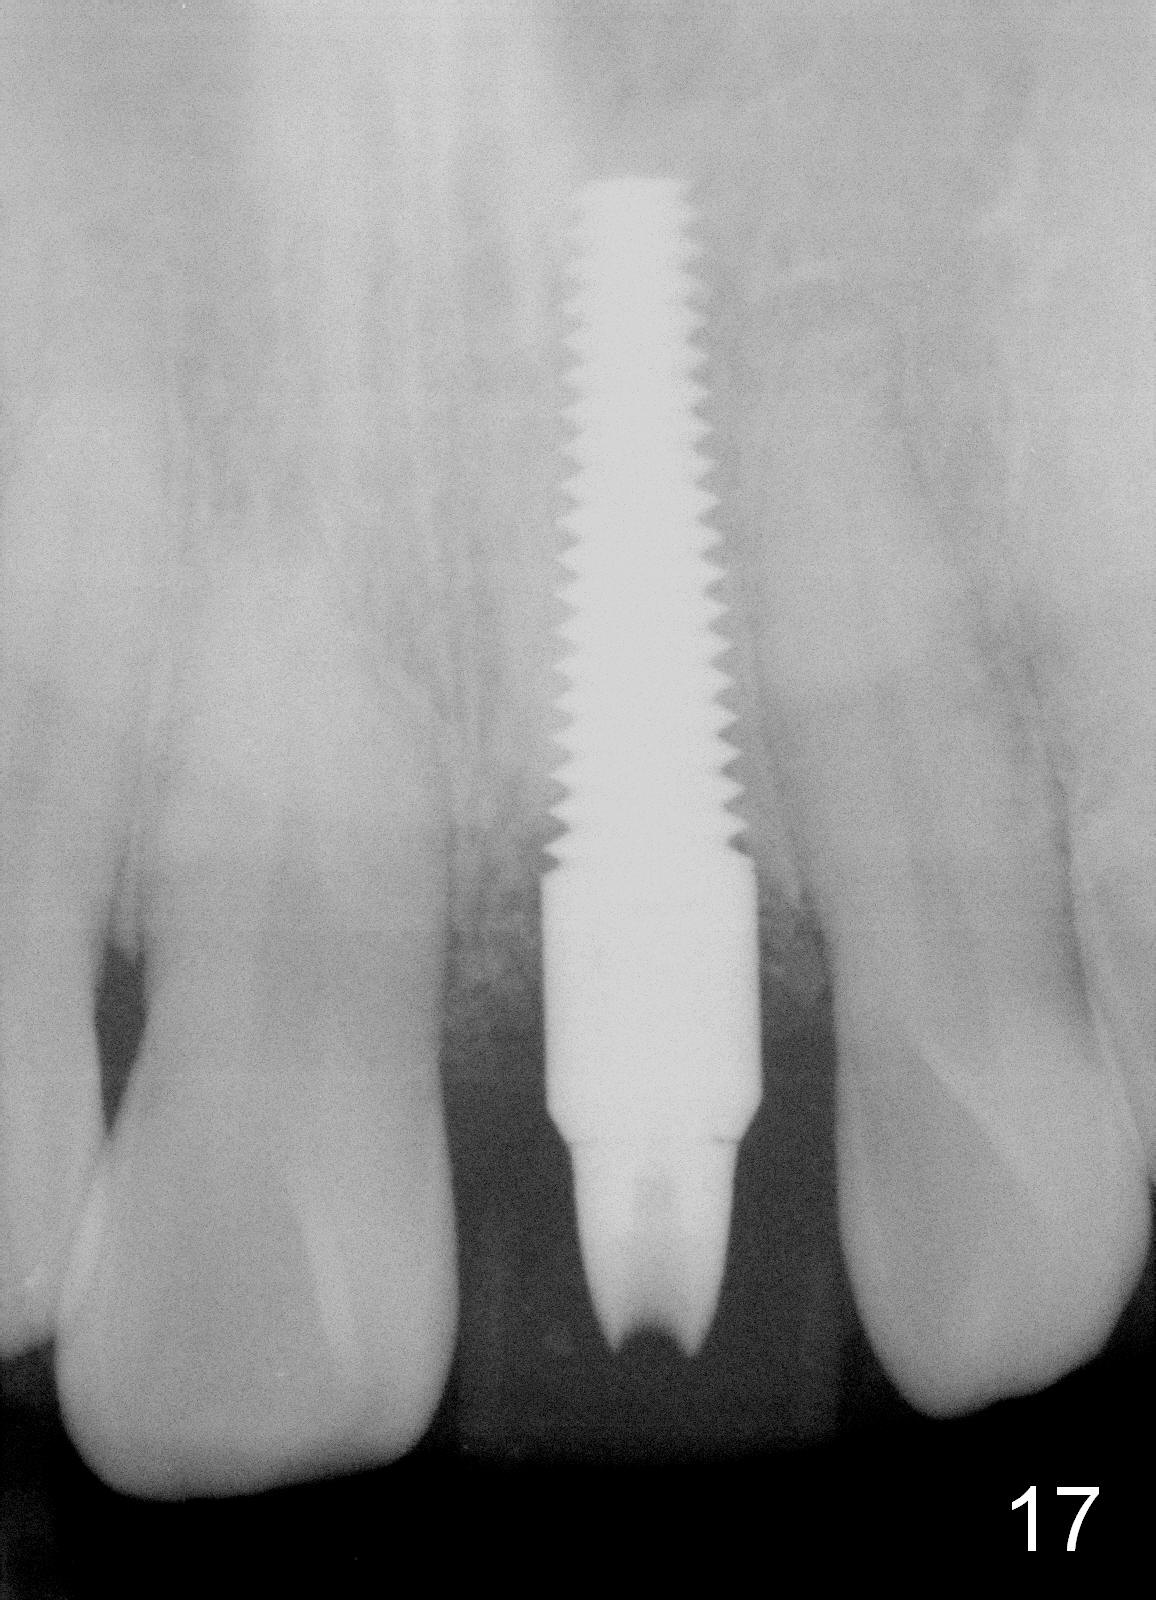

Bone expansion allows the implant (Fig.9 I) to have primary stability (insertion torque between 50 and 60 Ncm), since the cortex of the incisive canal is apparently intact.  Allograft is placed in the labial gap (Fig.10, 11 *) following installation of the abutment (A).  Finally an immediate provisional (Fig.10,12 P) is cemented.  Fig.13,14 are taken 8 days postop.  The patient returns 3 months postop (Fig.15,16).  Osteointegration appears to have occurred (Fig.15 arrowheads) and is more obvious 9 months postop (Fig.17).